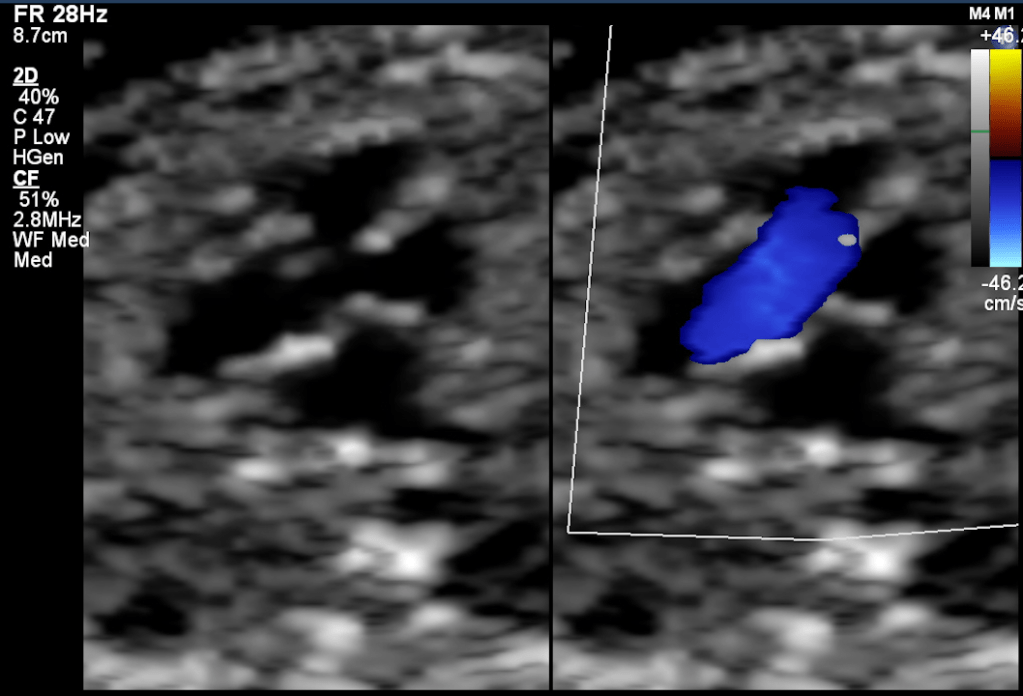

Smaller VSDs are much more common than a large defect. Also, the smaller defects are much more difficult to diagnose in early pregnancy fetal echocardiography because both the ventricle has similar pressures. Thus there is no significant color doppler flow can be seen across small VSD during most of the cardiac cycle. The 2D echo image also can miss a small VSD because of pixel spread of image due to significant magnification used during the echo.

The membranous defects pose a different kind of challenges to diagnoses by fetal echocardiography. This part of the septum is thin thus can appear as drop-out even in the absence of VSD there. Also, during color doppler, the color spill due to increase flow velocity of the outflow tract and great arteries crossover. Thus over-diagnosis is also common, and to avoid over-diagnosis, sometimes the diagnosis can be missed as well.

The presence of additional findings such as Tricuspid regurgitation (TR), Chambers / Arterial size discrepancy, along drop out at the septum might be an indicator of the presence of a ‘true VSD.’